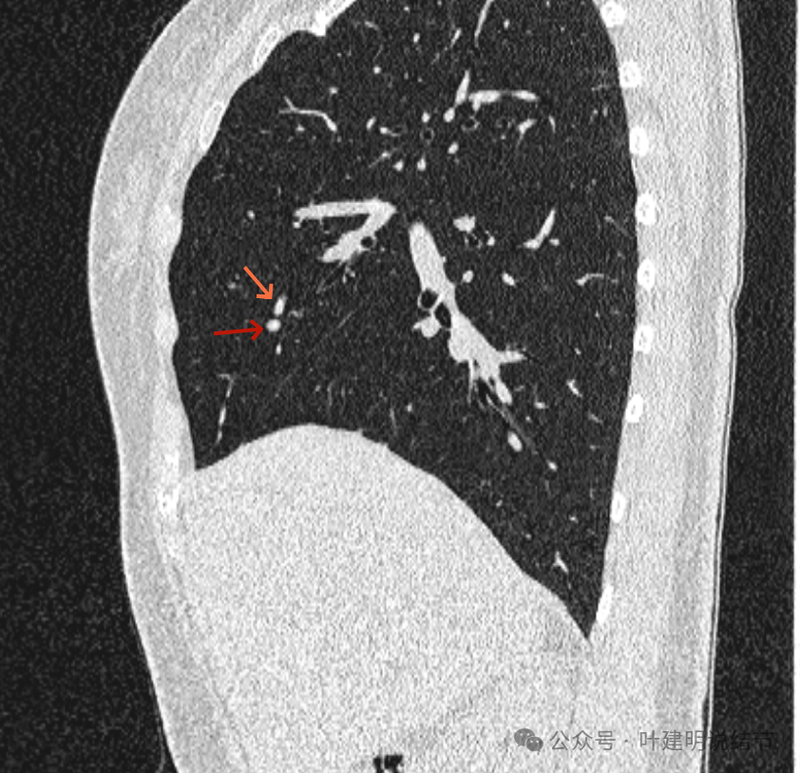

再看矢状位影像:

桔色的是血管,红色的是病灶,两者之间有间隙仍用天蓝色细线标注。

紧挨但仍有缝隙的。

血管贴着病灶,病灶表面略有毛糙之处。

血管有形成轻微血管弯征,两者紧贴。

两支血管夹着病灶,密度不同,有低密度间隙。

病灶与两侧血管关系均密切,明显觉得密度是不一样的,血管的密度略高,结节的略低。

病赤与血管在蓝色箭头处失去间隙,像是侵蚀血管壁,造成血管受侵犯破坏。病灶是软组织密度的,而且整体看有膨胀感。

病灶密度稍不均。表面不光滑。

病灶与边上血管间隙不清。

桔色箭头所示的血管受压稍有移位。

密度不同,关系密切。

边缘区域也是有膨胀感。

血管与病灶脱开后的样子。

边缘区也是基本上实性的。